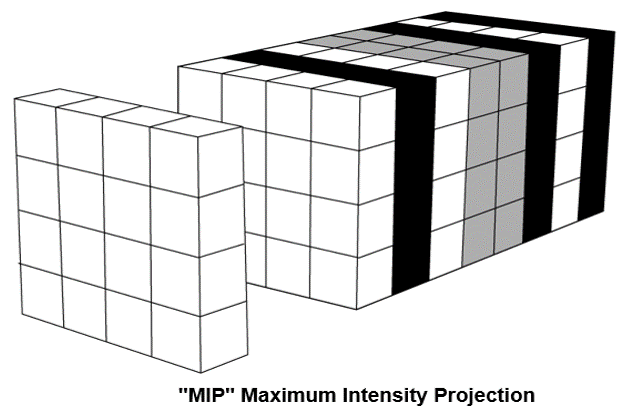

Maximum Intensity Projection: MIP

The maximum intensity projection consists of projecting the voxel with the highest attenuation value on every view throughout the volume onto a 2D image. An image that displays the maximum intensity for each pixel point on a thickened reformat plane.